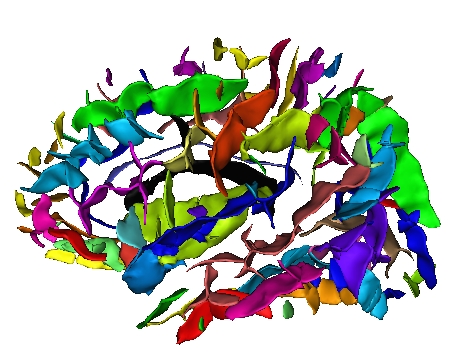

Each fold includes several buckets of voxels corresponding to the topologically simple surface making up its core (GREEN), its bottom lines (including branche's bottoms) (RED) and a few additional voxels corresponding to small or spurious branches (CYAN). Here is the example of a central sulcus:

You can get images of the bottom, of the simple surface or the sum of everything. You can also get the junction between each sulcus and the brain hull, which corresponds to the line which is sometimes drawn manually by some teams. Anatomist's viewer show you the result (the eyes):